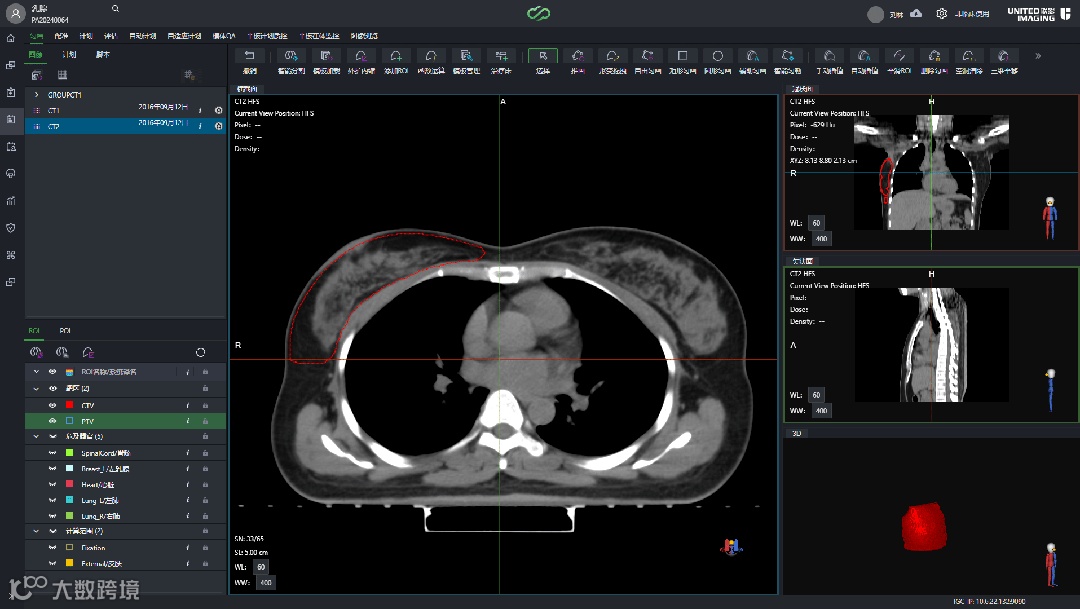

这个方法不只可以用于靶区之间的外扩关系,还可用来生成更多更复杂的辅助结构,如扩环、作辅助优化的靶区、生成Fix结构等,比如下图所示。

灵活利用带“钩子”的勾画模板,可为日常工作带来更多效率提升。